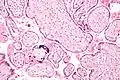

| Micrograph of cytomegalovirus (CMV) infection of the placenta (CMV placentitis), a vertically transmitted infection: The characteristic large nucleus of a CMV-infected cell is seen off-centre at the bottom right of the image, H&E stain. | |

CMV placentitis